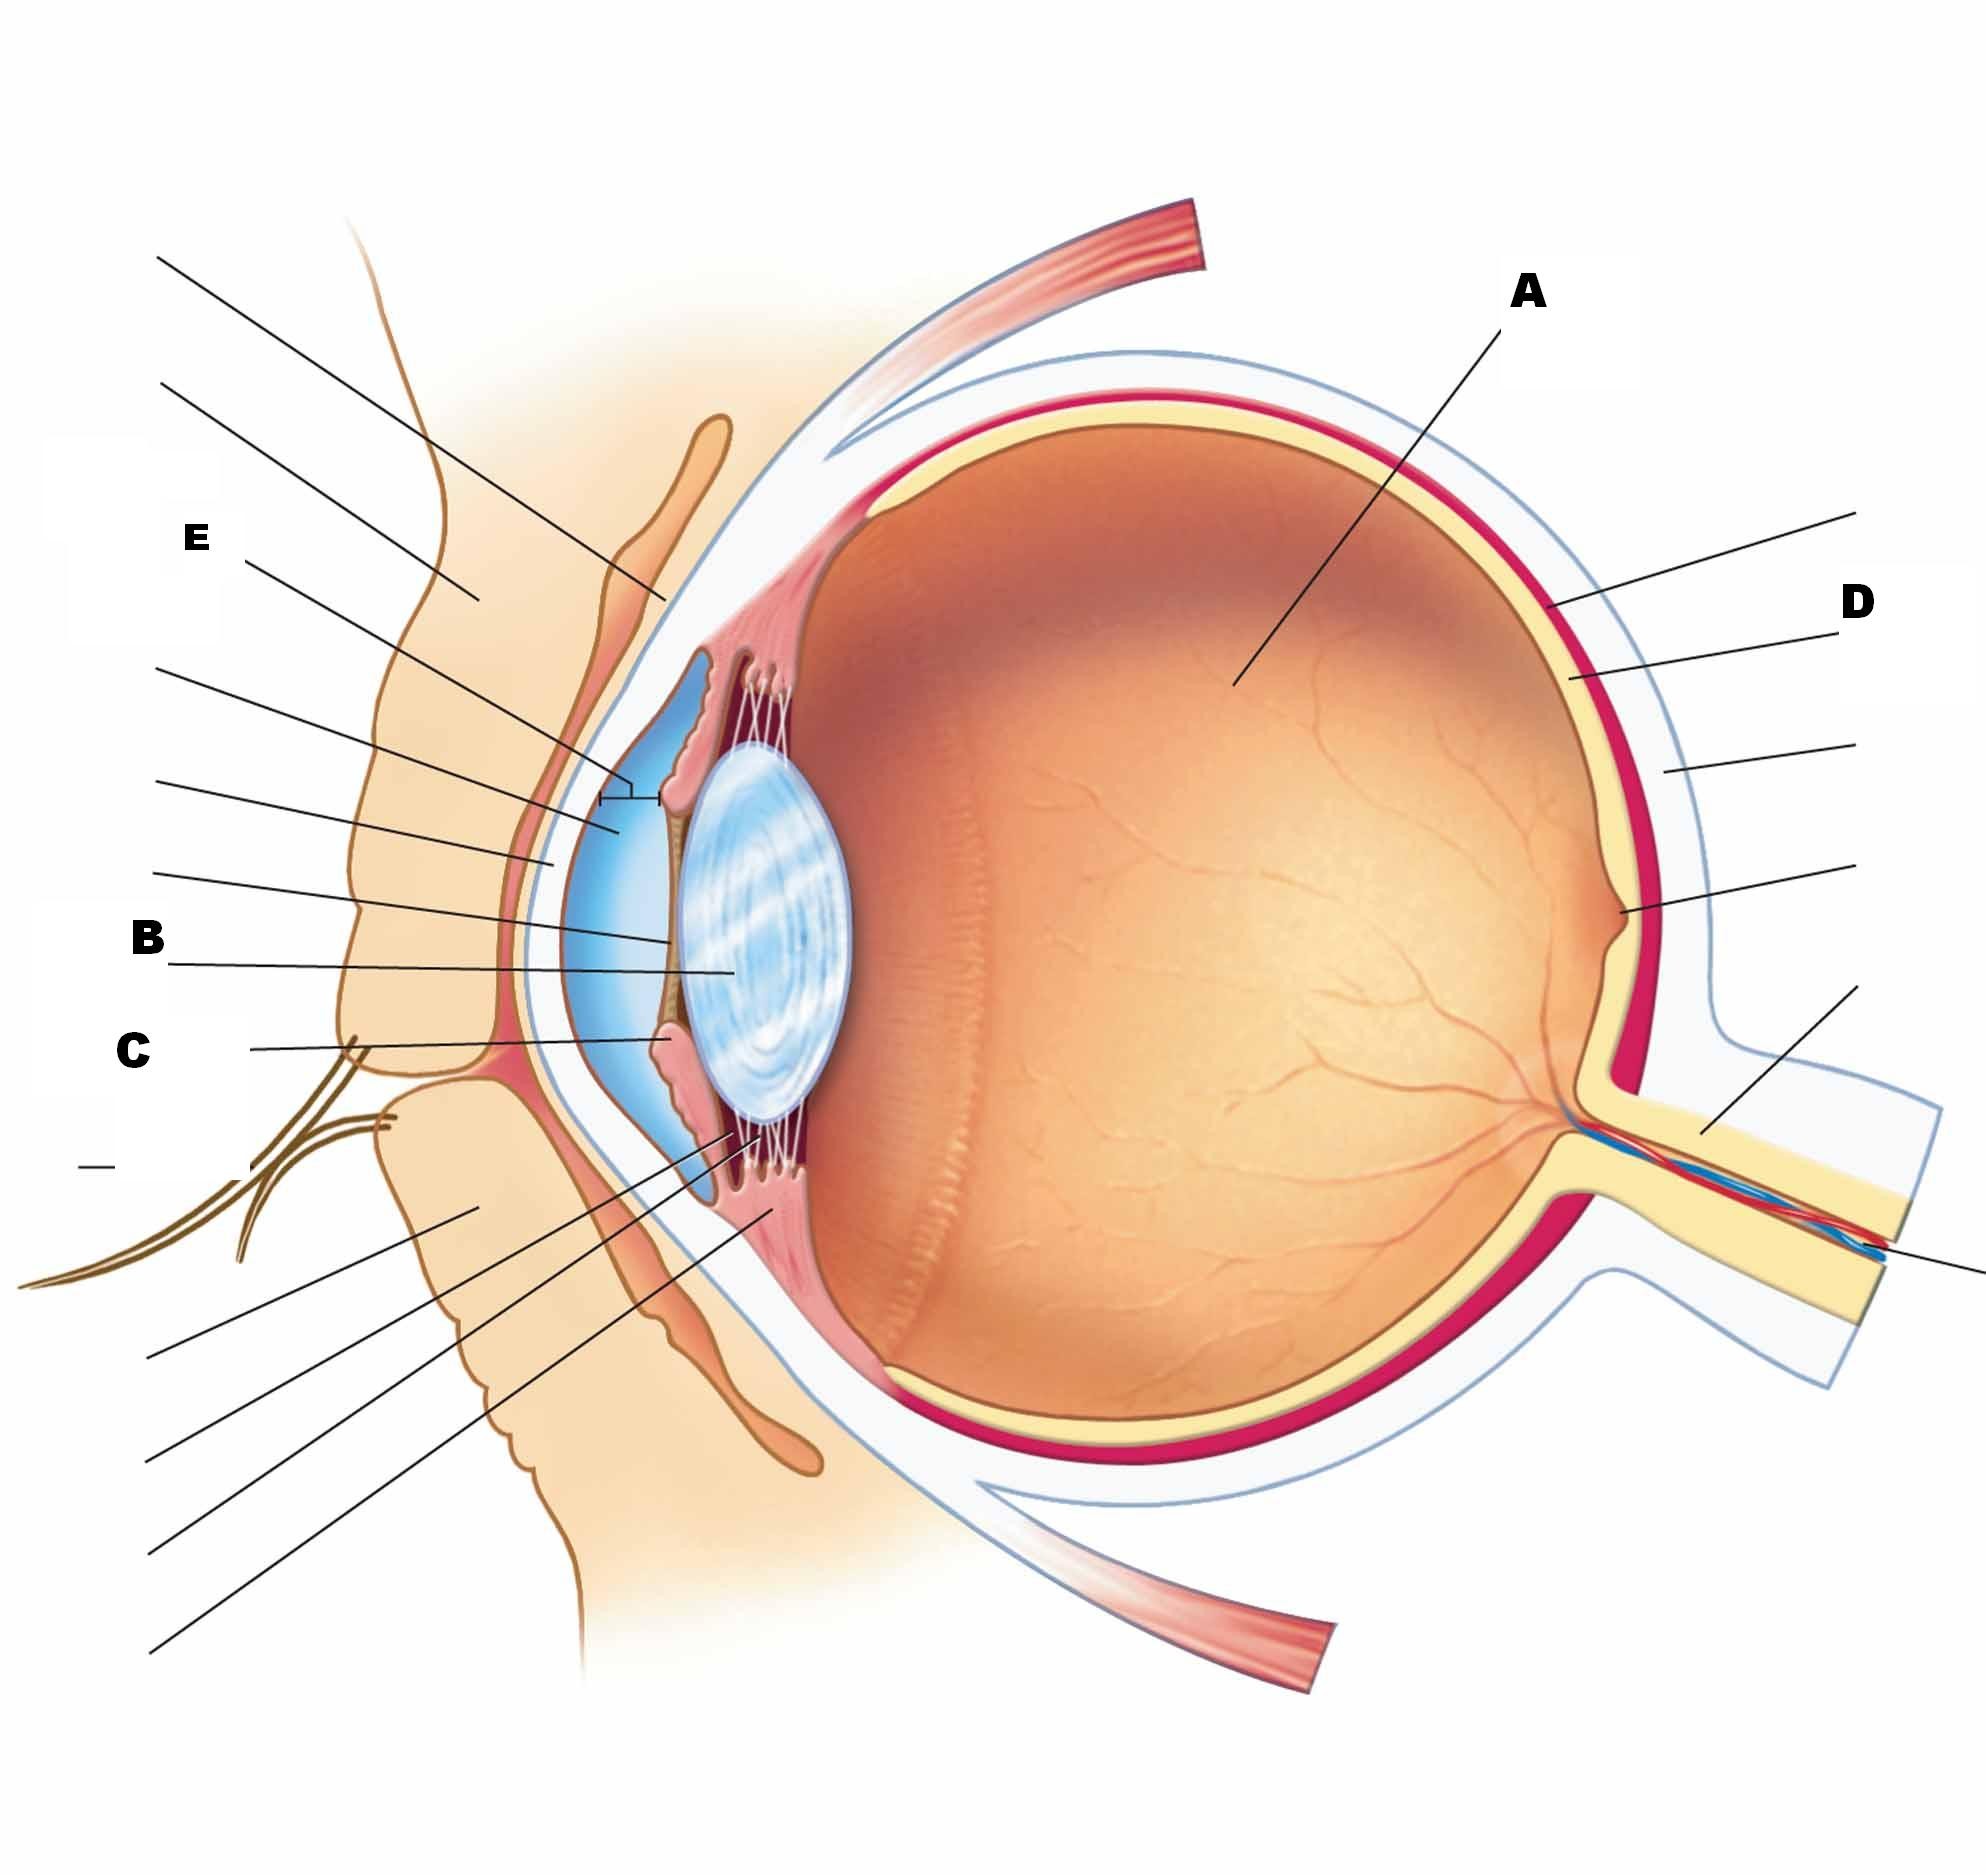

КТ-графики и изображение строения глаза